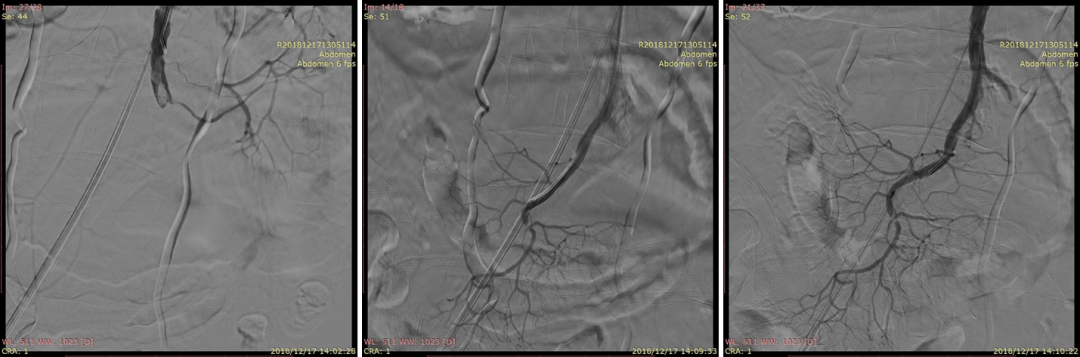

20230524DSA夹层动脉瘤

20230524DSA:VB支架植入

20230524DSA:仍有造影剂进入假腔

20230524DSA:再次送入VB